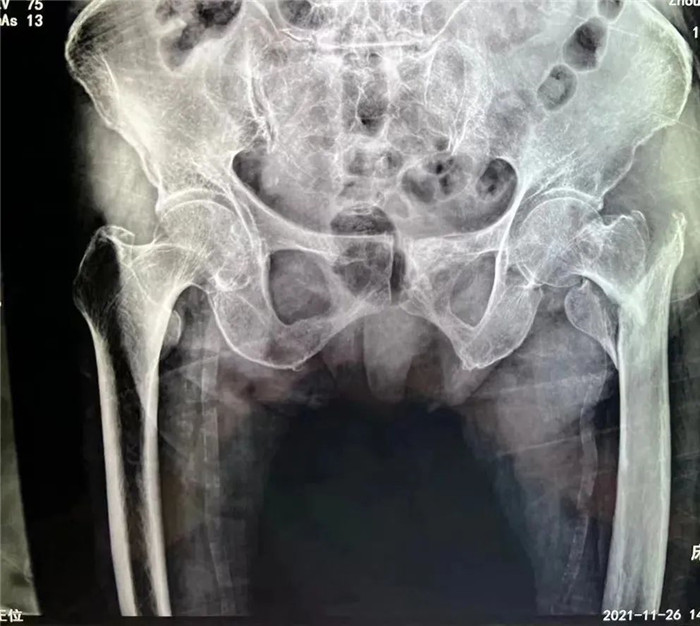

洪阿婆家住東港,前段時(shí)間在家行走時(shí)不慎摔倒,疼痛難忍,無(wú)法活動(dòng)。家人遂即送至我院,診斷為股骨粗隆粉碎性骨折。這是一種老年人常見(jiàn)的損傷,多是在摔倒時(shí)暴力導(dǎo)致股骨近端骨質(zhì)連續(xù)性斷裂,造成骨折。但是因老人年事已高,同時(shí)伴有腦梗死、肺部感染等多種并發(fā)癥,無(wú)論采取保守治療還是手術(shù)治療,都存在一定風(fēng)險(xiǎn),聽(tīng)到這話的家屬異常沉重。

在手術(shù)團(tuán)隊(duì)及患者家屬的大力支持下,羅軍主任團(tuán)隊(duì)為洪阿婆實(shí)施了閉合復(fù)位INTERTAN內(nèi)固定術(shù)。雖然手術(shù)風(fēng)險(xiǎn)較大,但憑借精湛的技術(shù)及豐富的臨床經(jīng)驗(yàn),手術(shù)十分成功而且僅僅用了1個(gè)小時(shí),術(shù)中出血不多,術(shù)后患者恢復(fù)得很好,第二天就可以在起床活動(dòng),極大的提高了患者的生活質(zhì)量,避免了長(zhǎng)期臥床造成的并發(fā)癥。